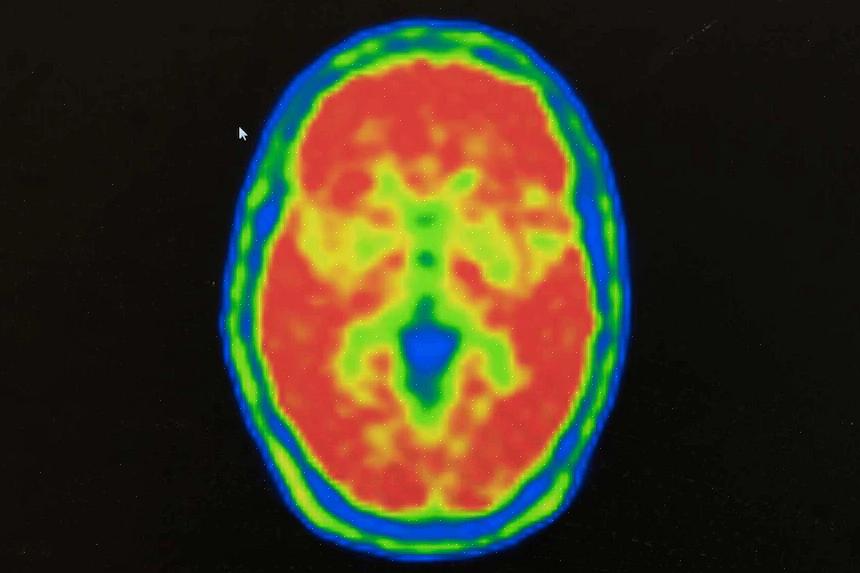

הם רצו לחקור את פעילות המוח, אז הם שמו אלקטרודות על פני המוח. המטרה העיקרית כאן הייתה להבין את כל הדברים שבאו לידי ביטוי במוות מוחי. הם גם רצו לדעת אילו אירועים נוירולוגיים התרחשו בזמנים אלו.

והם באמת עשו את זה! הם הצליחו לצפות ישירות במה שנקרא "צונאמי מוחי". הם צפו בגל הפרשות החשמליות שעוברות על פני כל המוח וגורמות לנזק בלתי הפיך. זו תחילת הסוף עבור תאי המוח שלנו. זה הרגע המדויק שבו הם נכבים לנצח, מה שמוביל למוות בלתי נמנע.

צונאמי מוחי יכול להתרחש אפילו 5 דקות לאחר שהלב שלך הפסיק לפעום. אז נראה שגם ללא דופק, הנוירונים שלנו יכולים להמשיך לעבוד. אבל ברגע שהלב שלך עוצר, הנוירונים מתחילים לאבד לאט לאט את הפוטנציאל האלקטרוכימי שלהם. זוהי תופעה שמדענים מכנים דפולריזציה עצבית.

המוח הוא אחד האיברים האנושיים שאנחנו עדיין יודעים הכי פחות עליהם. אבל במהלך העשורים האחרונים היו הרבה צעדים גדולים קדימה, במיוחד הודות לטכניקות הדמיה עצבית. התגלית הגדולה שלהם עשויה "להוביל לשיפור הליכי האבחון והטיפול בעתיד", כפי שאמר ג'נס דרייר עצמו.